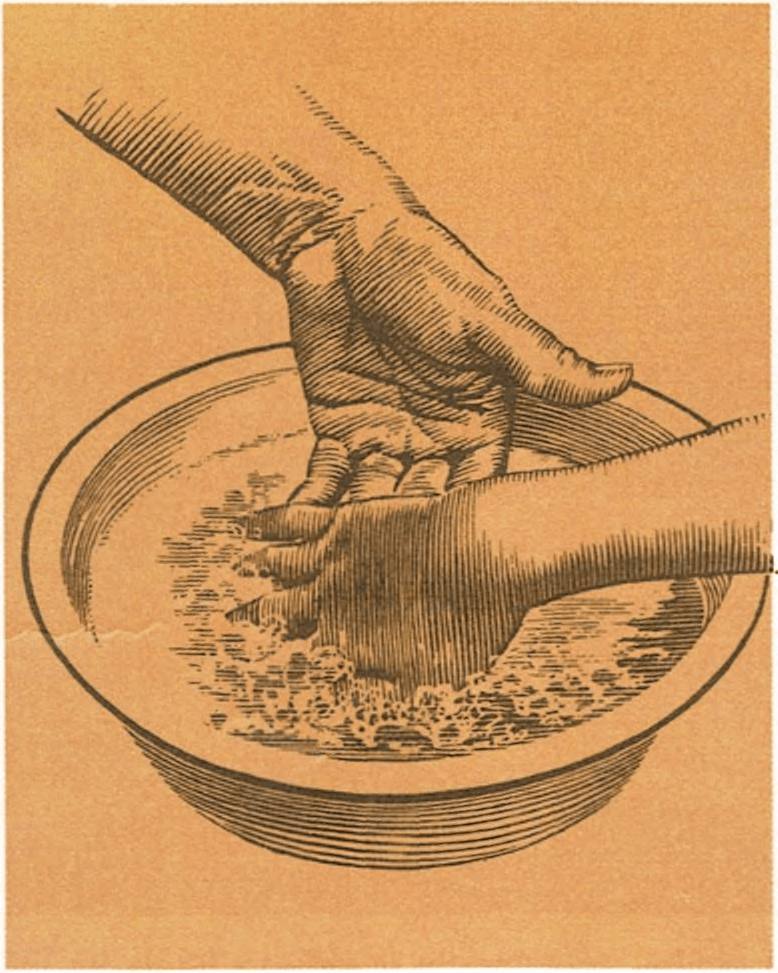

La primera es una contracción muscular con lesión persistente y dolorosa, generalmente en la parte anterior del muslo, provocada por un golpe o una distensión del músculo, que desgarra y aplasta las fibras musculares, provocando una pequeña hemorragia interna. Estas lesiones se dan sobre todo en los juegos de fútbol u otros deportes duros. El niño siente dolor cuando estira la rodilla o cuando la dobla más de un ángulo recto. La parte anterior del muslo se vuelve “azul” y frecuentemente se forma un bulto duro en el músculo. Las fibras musculares rotas pueden sangrar internamente durante varios días. Para aliviar el dolor y reducir la hemorragia, es recomendable la aplicación de hielo en la zona afectada; los baños calientes ayudarán a que el niño vaya recuperándose gradualmente.